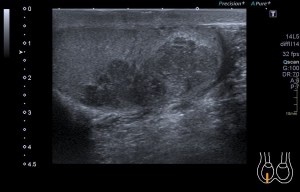

Al llegar al compartimento 6 me encuentro un tendón engrosado de tamaño y aspecto heterogéneo típico de afectación por tendinosis, con líquido en la vaina, te lo señala la imagen con flecha amarilla. Lo recorro y confirmo los hallazgos eje corto y eje largo, hago medidas y compruebo el doppler que marca Neovascularización asociada.

Observa las tres imágenes superiores, son muy ilustrativas, son comparativas de normalidad hallazgos patológicos, el izquierdo claramente patológico y el derecho claramente normal.